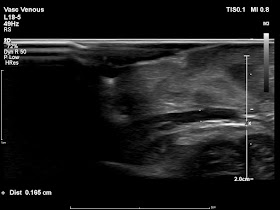

在這麼小的早產兒做心導管,面對的第一個困難點在於如何建立血管通道供導管進入。他們的股靜脈大小大約在1.5到2 mm左右,只要幾次穿刺失敗,局部有血腫,就足以完全壓扁原本的血管管腔。因此我們使用同步超音波導引穿刺血管的方法,隨時看清楚針尖位置,大幅增加成功率並避免誤刺動脈。插入股靜脈的血管鞘(通道)粗細也僅些微大於1 mm。

| 血管橫截面的超音波影像,圖中標示的是左股靜脈 |

| 血管縱向的超音波影像,途中標示的是左股靜脈 |

一個月後再追蹤下肢血管超音波,手術時穿刺的左股靜脈和未穿刺的右股靜脈相比,大小相當,沒有任何狹窄。目前也沒有呼吸道阻塞或吞嚥困難的症狀。